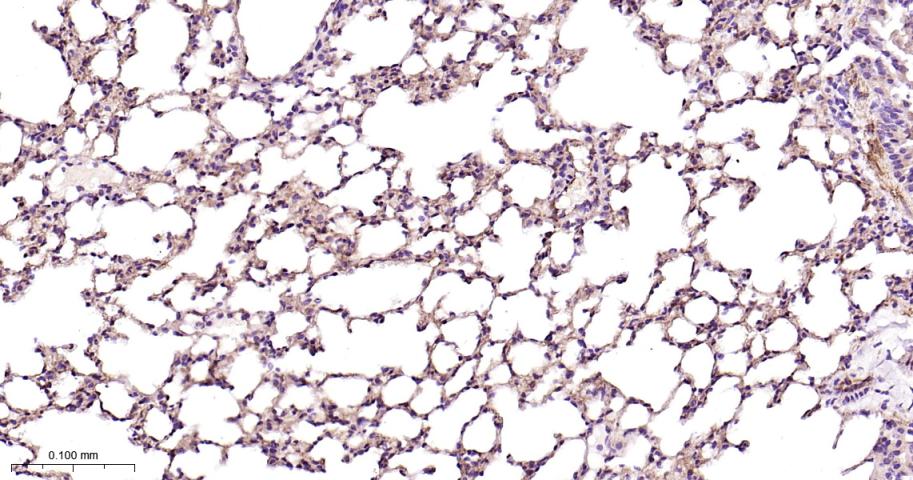

Paraformaldehyde-fixed, paraffin embedded Mouse Lung; Antigen retrieval by boiling in sodium citrate buffer (pH6.0) for 15 min; Antibody incubation with CD146 Monoclonal Antibody, Unconjugated(bsm-61136R) at 1:200 overnight at 4°C, followed by conjugation to the bs-0295G-HRP and DAB (C-0010) staining.